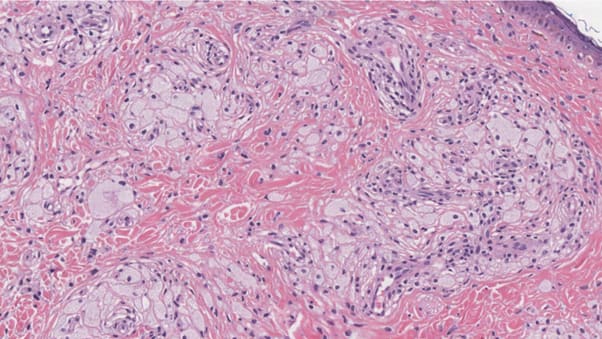

Гістологія

Ксантелазма складається з великої кількості гістіоцитів1, наповнених ліпідами. Ці клітини часто називають “пінистими гістіоцитами”2,оскільки їх внутрішній вигляд нагадує заповнення прозорою піною.

“Пінисті гістіоцити” в ксантелазмі значно більші за звичайні гістіоцити через накопичення ліпідів.

Гістологічний препарат ксантелязми під мікроскопом